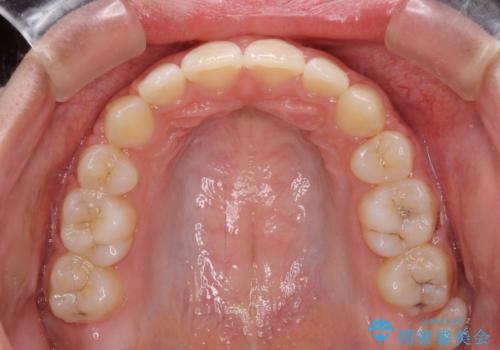

- 上下の出っ歯を気にして来院された患者様です。

口元を積極的に引っ込めるために、上下左右の第一小臼歯を4本抜歯することとしました。

前歯部の突出と開咬は、舌突出癖によるものでしたので、舌のトレーニングをしっかりと行っていただき、1年半程度と短期間で治療を終えることができました。